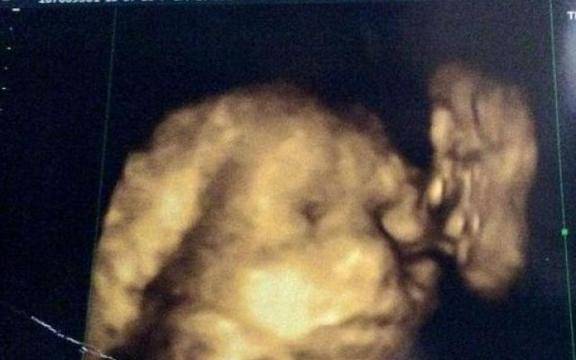

Алена Авдеева от областта Челабинск имала медицинска документация от лекар, в която се твърди, че е бременна и очаква близнаци.

Според документа, който е потвърден през януари тази година, тази 26-годишна жена е била в 9-ия месец от бременността. Изпратили я в Градската болница в Миас, където направила ултразвук, след което й казали, че тоновете на сърцата на децата вече не се чуват.

След спешна процедура й направили цезарово сечение, но след операцията последвал шок.

Авдеева всъщност не била бременна, а вместо плод в утробата носила киста, която била отстранена по време на операцията. Когато се върнала при своя лекар, без деца, всички били изненадани. Малко след като разбрали, че на жената била дадена грешна диагноза, всички нейни признаци, които имала по време на фалшивата бременност, мистериозно изчезнали.